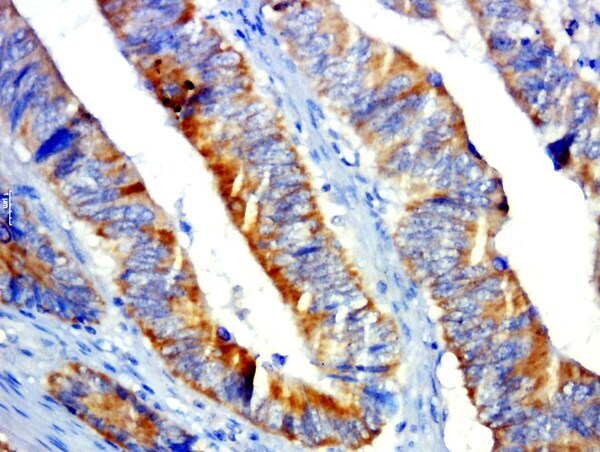

Supportive validation

- Submitted by

- Invitrogen Antibodies (provider)

- Main image

- Experimental details

- Paraformaldehyde-fixed, paraffin embedded human colon cancer; Antigen retrieval by boiling in sodium citrate buffer (pH6.0) for 15min; Block endogenous peroxidase by 3% hydrogen peroxide for 20 minutes; Blocking buffer (normal goat serum) at 37°C for 30min; Antibody incubation with GPR31 Polyclonal Antibody, Unconjugated (bs-13530R) at 1:500 overnight at 4°C, followed by a conjugated secondary for 20 minutes and DAB staining.